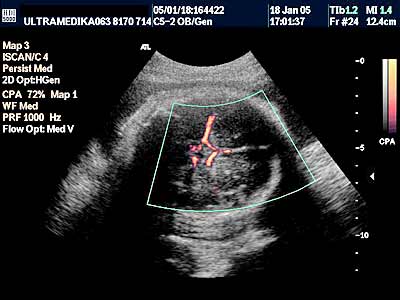

1. Arahnoidalne ciste ne bi trebalo da predstavljaju dijagnostički problem. One su avaskularne te se kolor Dopplerom (CD) ne dobija protok u njima. Ako postoji dilema koristi se kolor Power angio mod (CPA) (sl 010) koji registruje i protoke ekstremno malih brzina bez obzira na upadni ugao ultrazvučnog talasa u odnosu na krvni sud, što je osnovni preduslov za registrovanje protoka krvi, od pre 20 gidina poznatim konvencionalnim kolor Dopplerom . Mora se napomenuti da u toku pregleda u III trimestru trudnoće, jako često postoje nepovoljni uslovi za pregled (neadekvatan položaj ploda, neoptimalna količina plodove vode, debljina prednjeg trbušnog zida trudnice i položaj posteljice). U ovakvim situacijama aparati slabijih tehničkih mogućnosti, sa nižom cenom koštanja i posedovanjem klasičnog načina dobijanja ultrazvučne slike i kolor Doppler tehnike, imaju znatno ograničene dijagnostičke mogućnosti.

3. Arteriovenske malformacije su ispad prve faze embriogneze tj. histiogeneze. Ona započinje u toku 6-11 nedelje gestacije kada ne dolazi do formiranje moždanih kapilara. Rezultat ovoga je direktna komunikacija između cerebralnih (moždanih) arterija i dubokih drenažnih vena mozga. Ovakva situacija dovodi do direktnog šanta arterijske krvi u vene, naime "zaobilaze“ se neadekvatno formirani kapilari u mozgu. Iako je greška nastala rano, tek sa ukupnim povećanjem volumena mozga i količine krvi koja kroz njega prolazi a koja nastaje u III trimestru, moguće je ultrazvukom registrovati vene koje su postale značajno proširene i aneurizmatske. Jedna od najčešće prisutnih patoloških komunikacija je tok krvi u drenažnu venu Galen-i. Njeno aneurizmatsko proširenje može dovesti do kompresije na mozak koji zaostaje u rastu -postaje hipoplazičan i atrofičan a može doći i do formiranja hidrocefalusa.

A) Savremena dijagnostika korišćenjem Broad band kolor Dopplera (Broad band-CD) i kolor Power Dopplera (CPD) bez obzira na količinu krvi koja prolazi kroz vaskularnu anomaliju i bez obzira pod kojim uglom je moguće poslati ultrazvučni talas, je u stanju da postavi dijagnozu ove ozbiljne vaskularne malformacije CNS. U nepovoljnim uslovima standardna ultrazvučna tehnika sa CD nije u stanju da prikaže ni normalne krvne sudove Wilisovog šestougla niti duboke drenažne vene . Jedino savremena ultrazvučna tehnika je u stanju da postavi dijagnozu bez obzira na položaj ploda koji obično bitno ne menja svoju poziciju u toku pregleda u III trimestru trudnoće. Takođe CPD tehnika je u stanju da proceni tačno hemodinamiku moždane i srčane cirkulacije i da tačnu prognozu. Ovo je važno jer se neke aneurizme vene Galen-i mogu lečiti nakon rađanja deteta embolizacijom krvnih sudova.